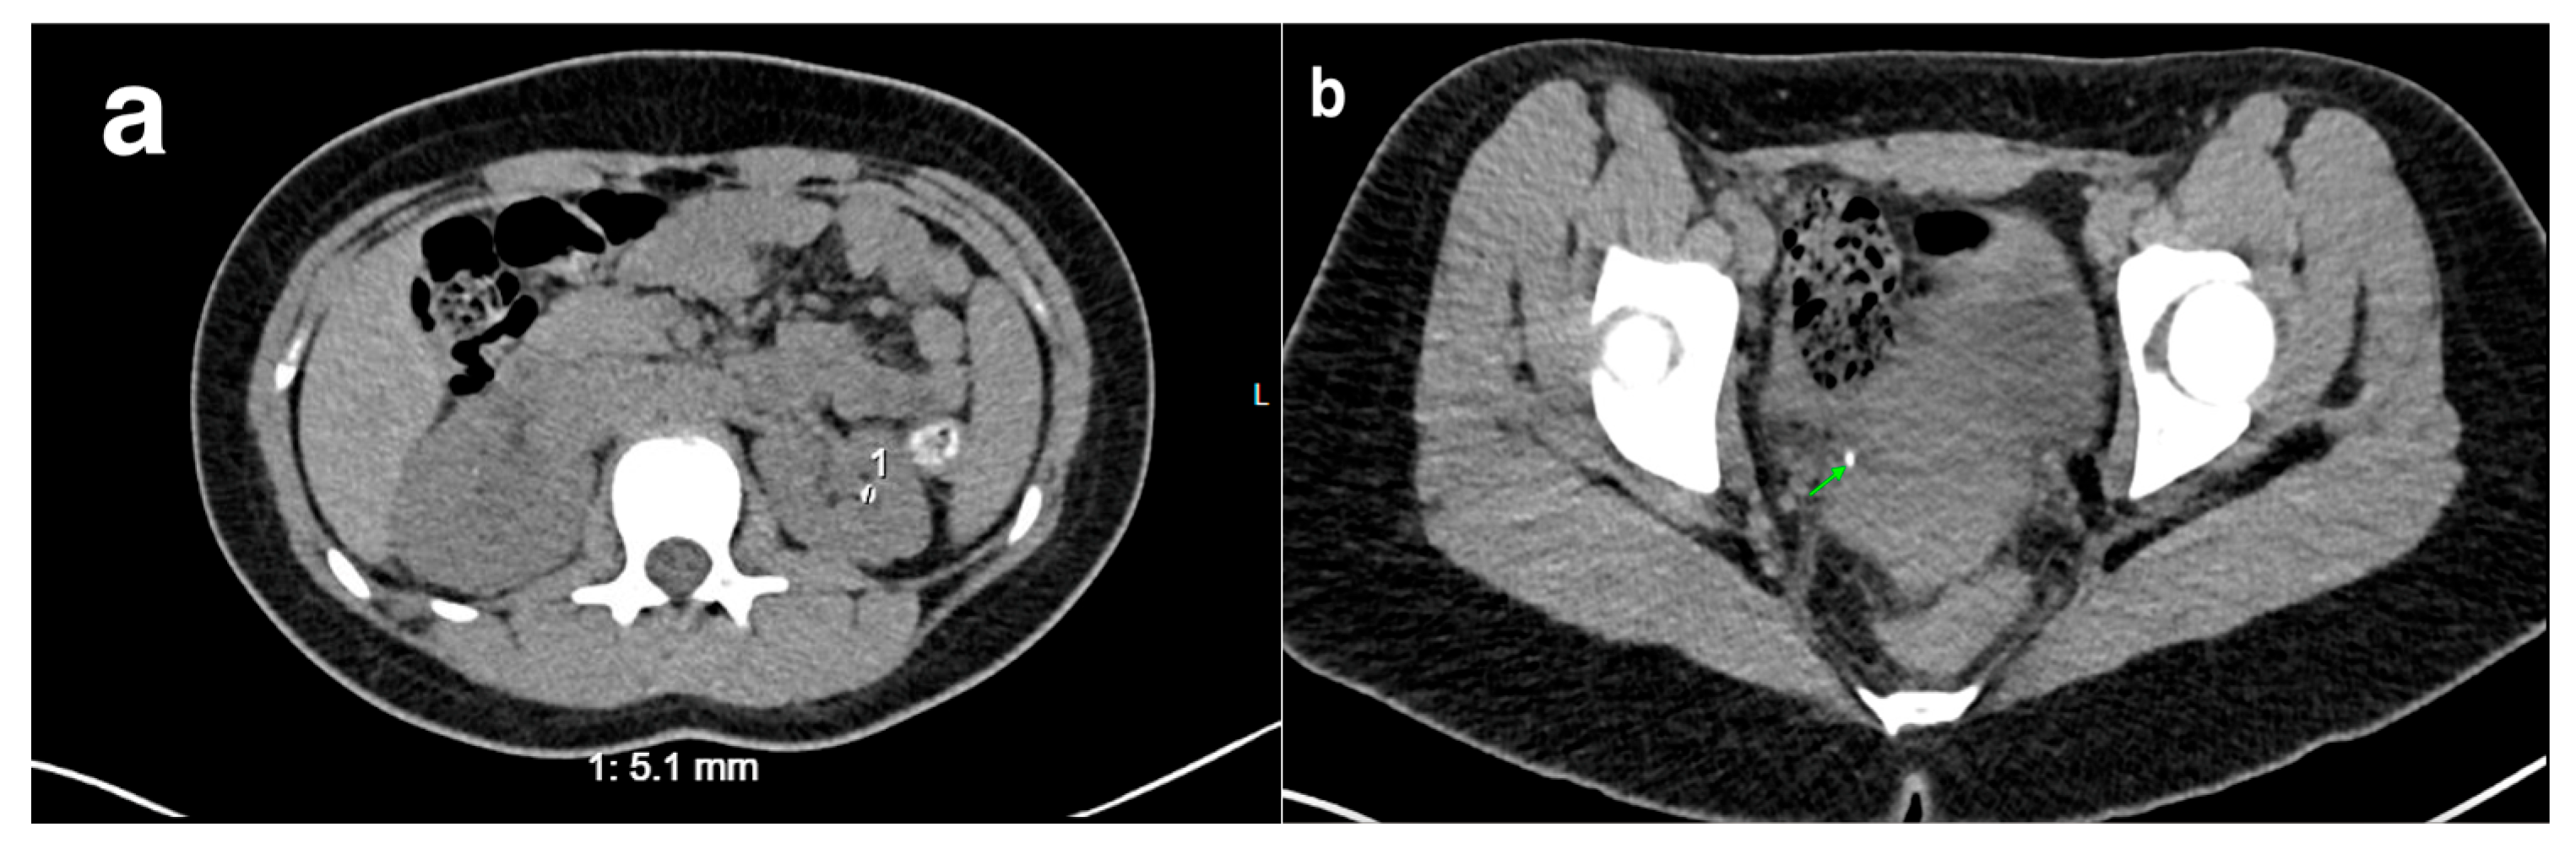

20. Nephrolithiasis

21. Trauma to the Urinary Tract